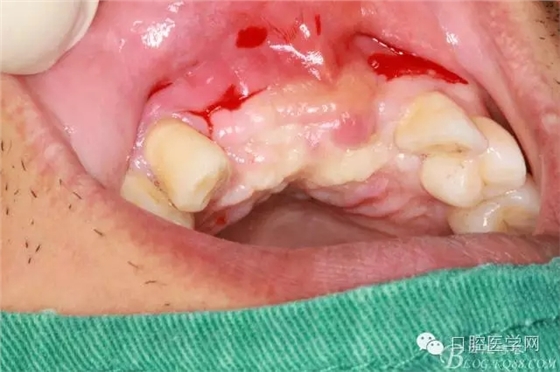

植入種植體左側(cè)3510,右側(cè)4010,植骨Bioss,蓋膜Cytoplast。骨膜減張垂直褥式縫合加間斷縫合。

遺憾沒(méi)有保留術(shù)前口內(nèi)照片,只有術(shù)后的。

之所以選擇Bioss是考慮其降解速度較慢,種植體接觸大面積為自體骨,Bioss可以很穩(wěn)定的緩慢吸收逐步引導(dǎo)骨再生。

后期的修復(fù)工作由之前的轉(zhuǎn)診醫(yī)生后續(xù)處理,由于GBR過(guò)程骨膜減張導(dǎo)致角化牙齦不足3mm,建議角化牙齦移植改變其更好的牙齦生物型。